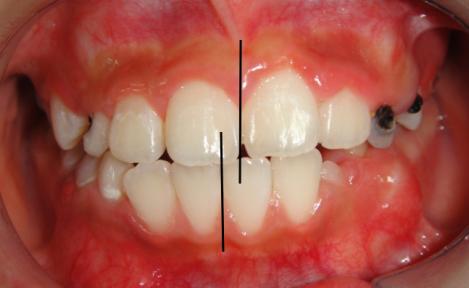

下图为早期矫治前后面型和口内像对比,可以看到矫治后的患儿面型左右基本对称,下牙列的偏斜程度也明显改善,前牙的反合得到解除,去除了上颌骨发育的不利因素。接下来就是等待患儿换完牙以后进行二期治疗,二期治疗可以从三维方向上控制牙齿的移动方向,进一步平衡咬合,使得矫治效果更加稳定。二期治疗的矫治器可以选择固定矫治器也可以选择无托槽隐形矫治器。

4.牙弓不对称

(图为单侧后牙反合一期矫治前后对比)